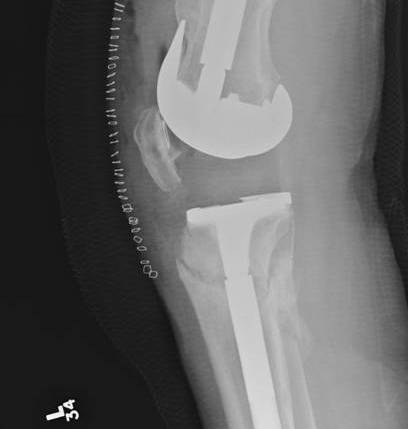

2.  Retrograde IM Nail

TKR Periprosthetic FractureTKR Periprosthetic Fracture 2TKR Periprosthetic Fracture Retrograde Nail 1TKR Periprosthetic Fracture Retrograde Nail 2